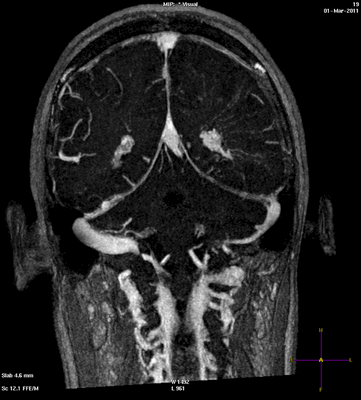

Стандартное лабораторно-инструментальное обследование пациентки (биохимический анализ крови, электрокардиография, рентгенография органов грудной клетки, ультразвуковое исследование сосудов шеи) патологии не выявило. Осмотр офтальмолога: состояние глазного дна — диск бледно-розовый, границы четкие, калибр сосудов не изменен. МР-веносинусография и КТ-ангиография с венозной фазой: крупные вены и синусы не изменены, за исключением умеренного расширения корковых вен среднего и дистального сегмента справа (на уровне верхней анастоматической вены Тролярда) (рис. 2), что может служить признаком формирования коллатерального оттока.

ткани [16]. Идентичность очагов при CLIPPERS с очагами нашей больной позволяют расценивать их как сосудистые. Наличие перифокального отека свидетельствует о вовлечении в процесс мелких вен. Подтверждением сказанного является формирование венозных коллатералей (см. рис. 2), локализация очагов в обоих полушариях головного мозга, симметричность их расположения, клиническая картина и, наконец, сама причина заболевания — тромбофилия.

симметричное расположение очагов; расширение коллатеральных вен; небольшие («с просяное зерно») очажки, окруженные перифокальным отеком объединенные в конгломерат, по данным нейровизуализиации;